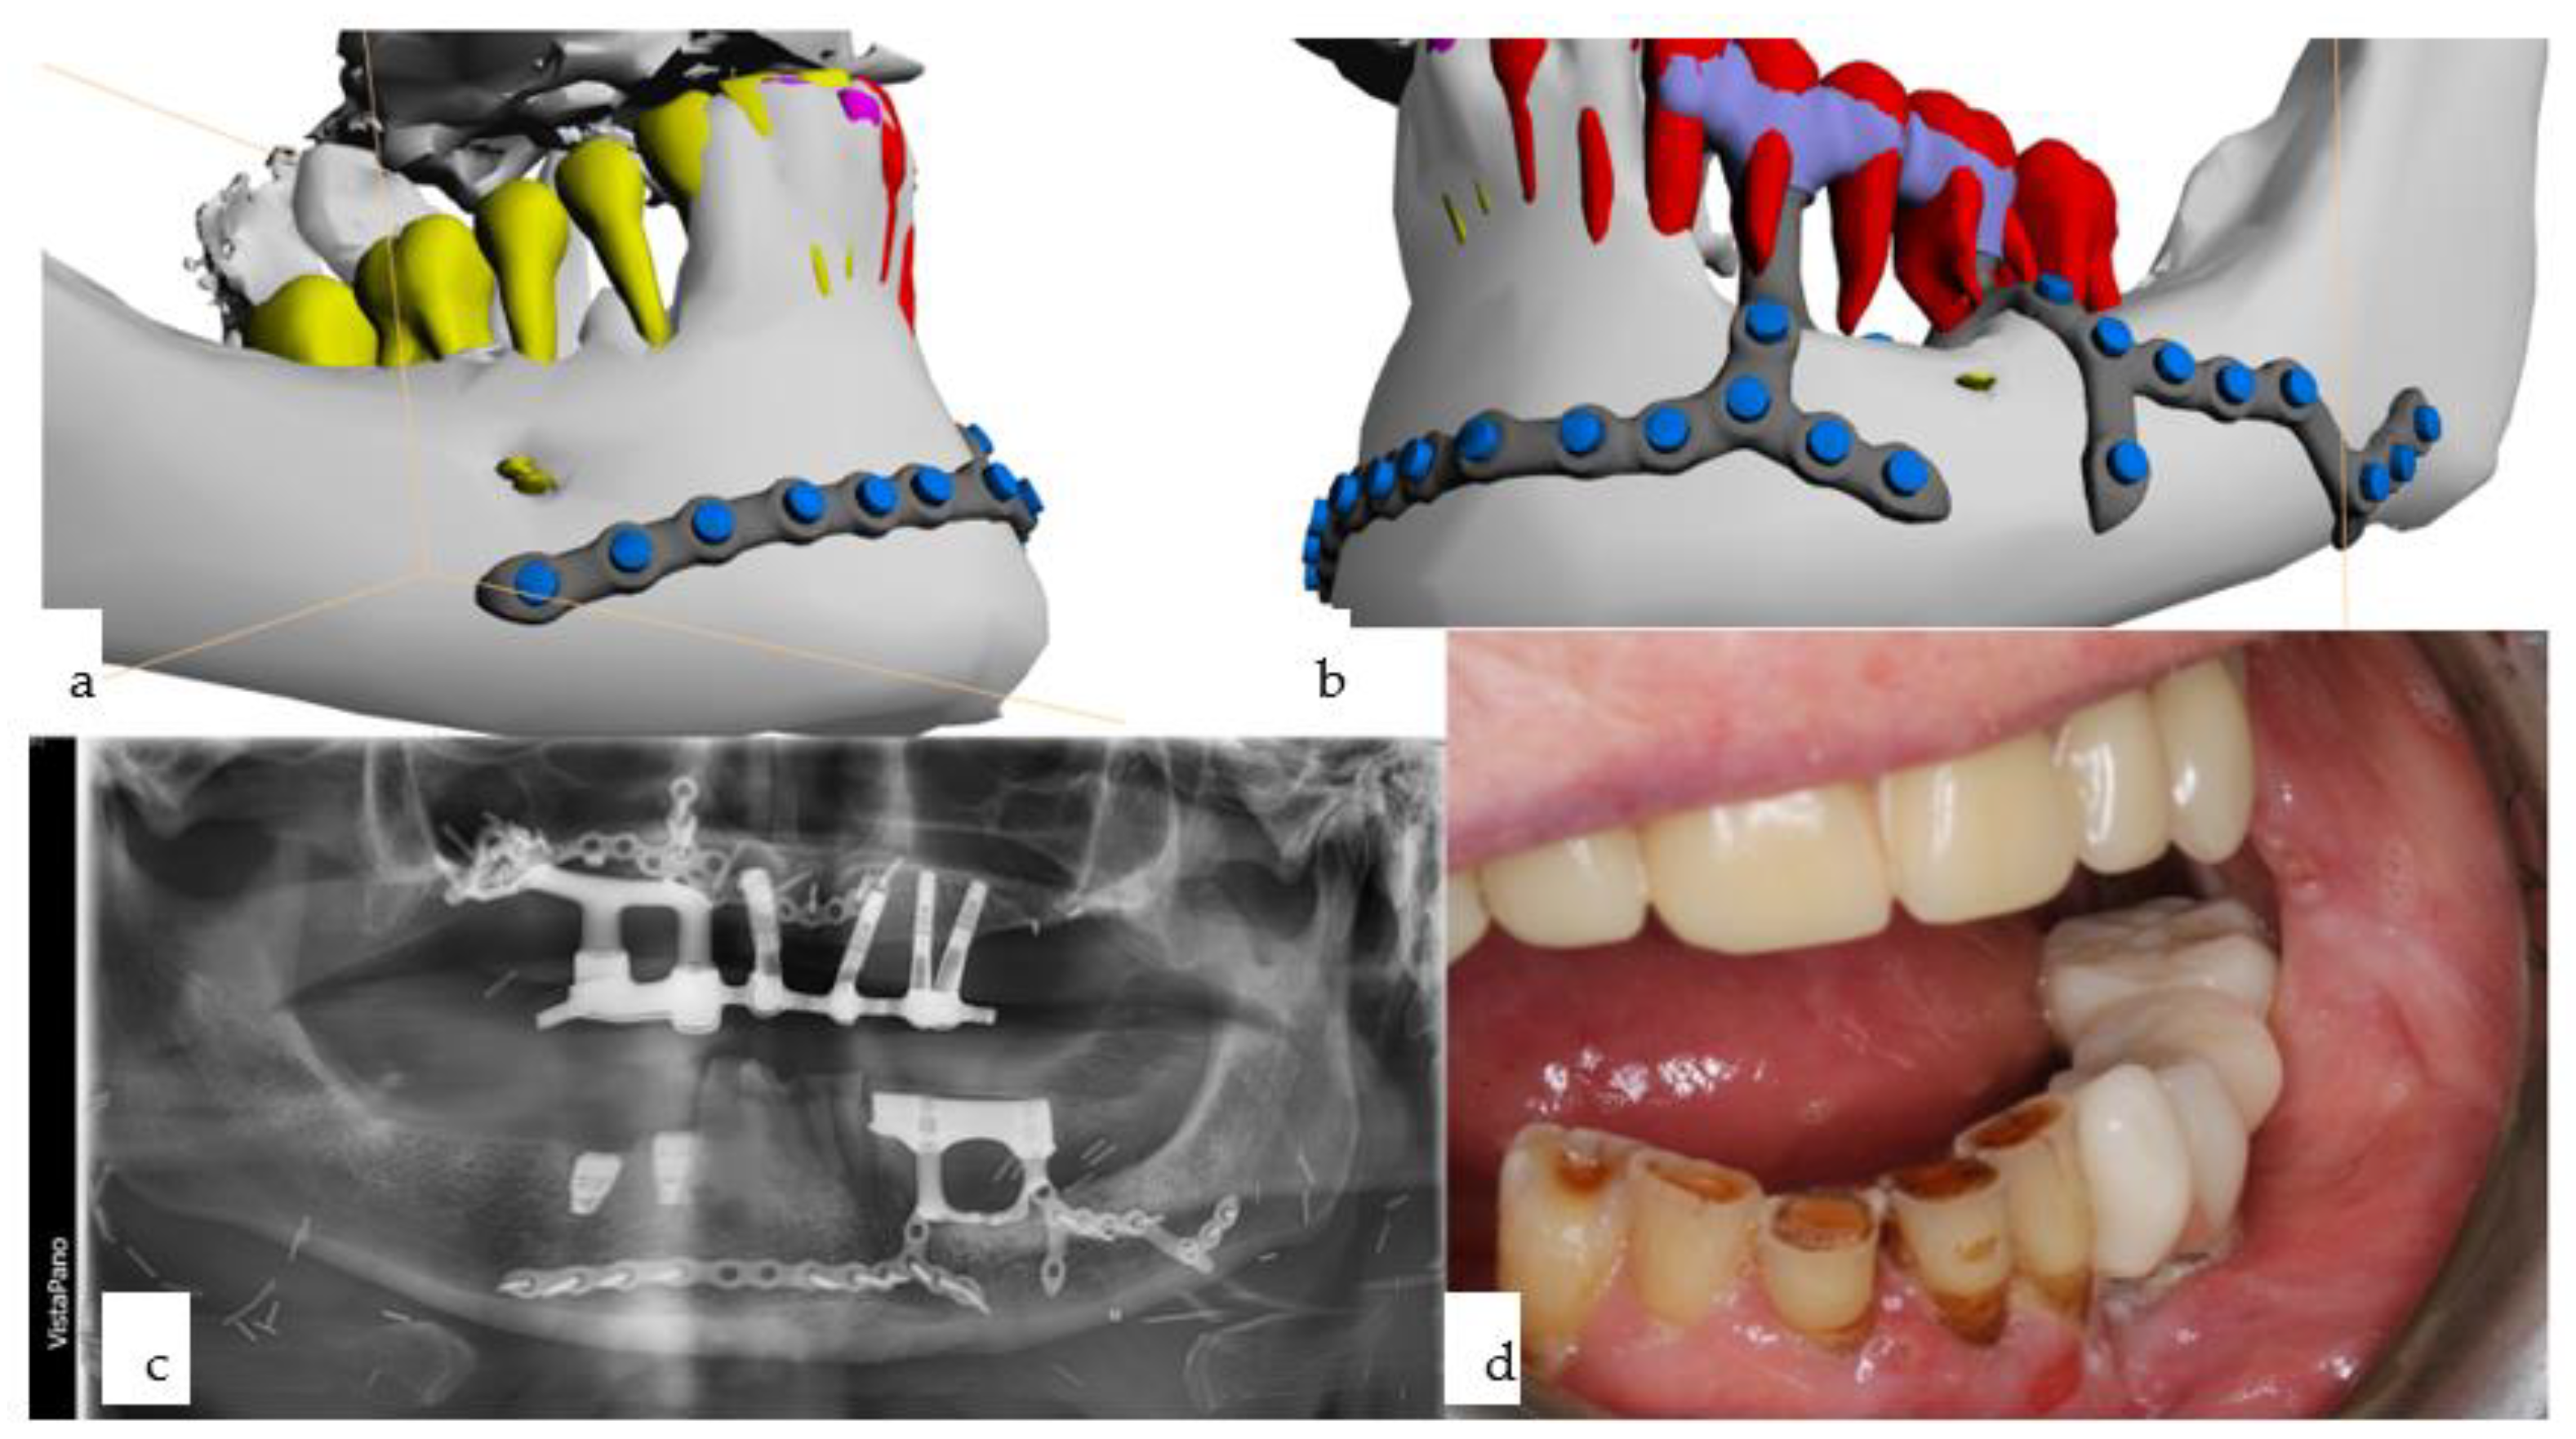

Marginal resection was performed, with alveolar bone removal posterior to the lower left canine followed by primary reconstruction using a microvascular prelaminated fasciocutaneous radial forearm flap (prelamination was provided by re-blepharoplasty of the upper eyelids), allowing separation of the horizontal (floor of the mouth) from the vertical (vestibule, lip, cheek) subunits (Figure 13 and Figure 14). Following final histopathology confirming R0 resection, a CAD/CAM subperiosteal implant was inserted 11 months later onto the left lateral mandible, with a boom running over the left mental foramen and projecting far posteriorly, while another boom was designed over the chin to the contralateral side, respecting the tooth roots (Figure 15). Multivector rigid fixation was provided by 17 2.0 screws ranging from 7 to 13 mm in length. Simultaneously, two conventional bone-level dental implants were inserted using guided surgery with a CAD/CAM drill guide designed with coDiagnostiX® 10.3 Software (Straumann, Basel, Switzerland). Twelve months later, the patient developed a fourth onset of squamous cell carcinoma of the anterior mandible, necessitating further marginal resection, including the remaining dentition of the mandible. Another microvascular radial forearm flap was used to reconstruct the intraoral tissues and separate the aforementioned subunits (Figure 16). Only the provisional prosthesis on the IPS Implants® Preprosthetic, together with the implant-borne overdenture in the maxilla, allowed retention of the occlusal relationship and definition of the vertical height.

Figure 15. (ad): Computer-assisted planning of the IPS Implants® Preprosthetic, along with a prosthodontic backward plan superimposed (a,b). Leaving out both mental foramina is ensured; anchorage is planned far away from the transition of the posts through the radial forearm flap (a,b). The orthopantomogram shows, in addition to the aforementioned implant, two conventional bone-level implants, placed using guided drilling, in the lower right first and second premolar region (c). The intraoral view displays the temporary prosthesis on the mandibular subperiosteal implant.